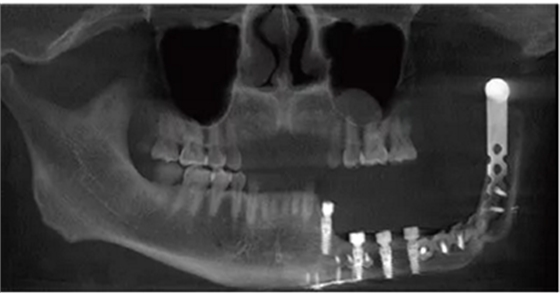

種植體植入后拍攝錐形束CT(cone-beam computed tomography,CBCT)顯示種植體在位,復(fù)合基臺(tái)對(duì)接在位,骨愈合良好(圖6)。